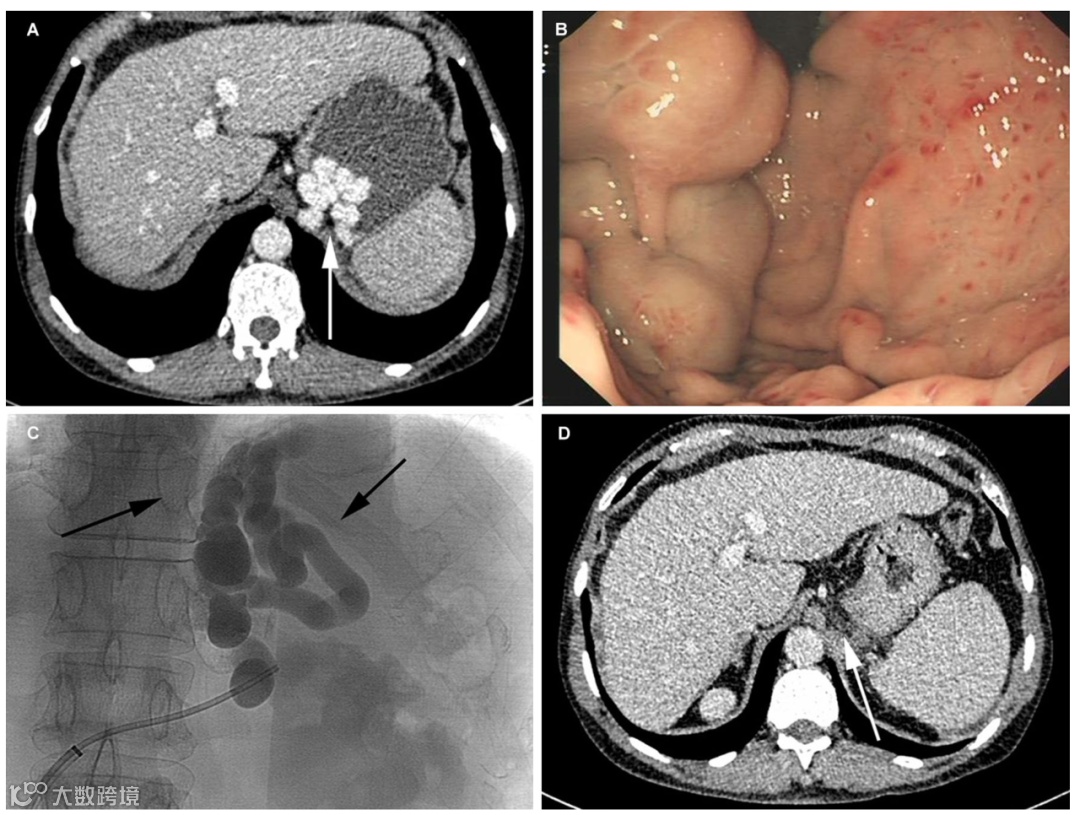

BRTO在日韩临床应用经验较多,发表论文也是国际上最多的,欧美国家近年来开展例数也在逐渐增加。目前BRTO技术国内发展不尽如人意,一方面是部分学者关注不够,理念上仍片面追求降低压力,另一方面也是缺乏合适的介入器械。四川大学华西医院一直在探索BRTO技术的规范化和国产化,并于2017年发表了基于华西经验的BRTO技术(图1)[9]。2014年至2015年,32例肝硬化合并GV出血患者在华西医院行聚桂醇泡沫硬化治疗,BRTO技术成功率为96.9%,仅有1例患者缺乏合适的球囊无法彻底封堵分流道。泡沫硬化可以大大降低硬化剂的使用量,减少硬化剂相关并发症,本组患者聚桂醇的平均用量为12.4 ml(8~20 ml)。BRTO术后2例患者新发门静脉血栓自行缓解,7例(22.6%)患者EV加重行内镜治疗,5例(16.1%)患者腹水加重。随访2年后2例患者死亡,31例患者经内镜或CT证实GV消失。